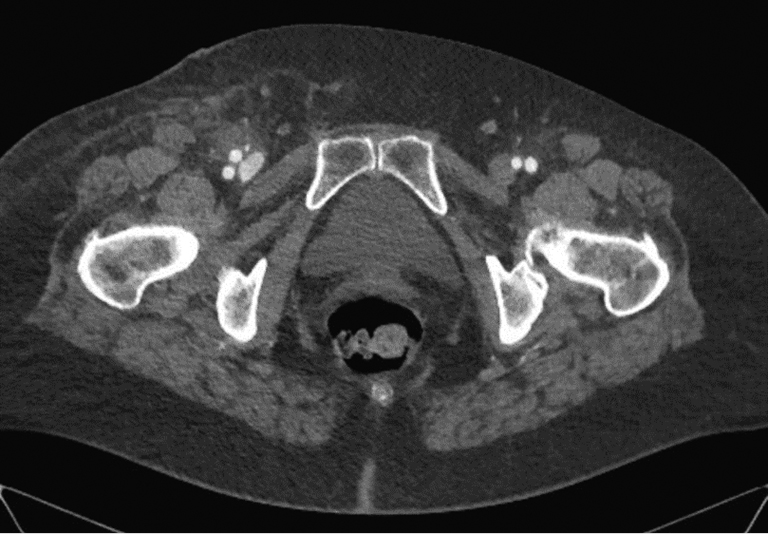

Hematoma of the puncture site is the most common complication, and it has been reported to occur in 5%–23% of cases by different authors. The hematoma scope varies from slight staining of the skin at the puncture site to a massive tumor requiring surgical treatment and blood transfusion. First, the causes of hematoma include multiple puncture attempts, incorrect or insufficiently long-lasting postoperative compression, and incorrect use of suturing devices. In the vast majority of cases, hematomas do not require special treatment and persist for 1–2 weeks. Follow-up and local therapy with heparin ointment are usually sufficient. If a growing hematoma is detected during the intervention itself, it is possible to use endovascular methods of treatment, such as balloon compression or implantation of a short stent or stent prosthesis. In this case, a contralateral approach is required. If it becomes necessary to implant a stent or a stent graft, it should be taken into account that the puncture site is anterior to the hip joint, that is, it is located in the mobile segment. The implantation of a stent in such a segment poses the risk of implant fracture and, as a consequence, the occurrence of vascular obstruction, limiting blood flow. Sometimes surgical treatment is necessary due to the hematoma size. The CT presentation of such a hematoma is shown in Figure 2. In case of the rapid development of a massive hematoma, necrotic changes in soft tissues are also possible. An example of such a case is presented in Figure 3. A special variant of local hematoma leads to the occurrence of a false aneurysm (0.5%–9%), and emergency surgery is indicated in this case.When performing postoperative compression, the size of the tool used to catheterize the vessel should be considered. The compression force should be approximately 20 mmHg above the systemic systolic pressure. The reference points in Table 2 can be used to determine the compression time. When using tools larger than 6 Fr in diameter for arterial access, the use of a suturing device is recommended. In the early postoperative period, strict adherence to bed rest by the patient and control of the puncture site by the department staff are of key importance.

Fig. 2. Massive hematoma in the right inguinal region and thigh after percutaneous coronary intervention (author’s case)